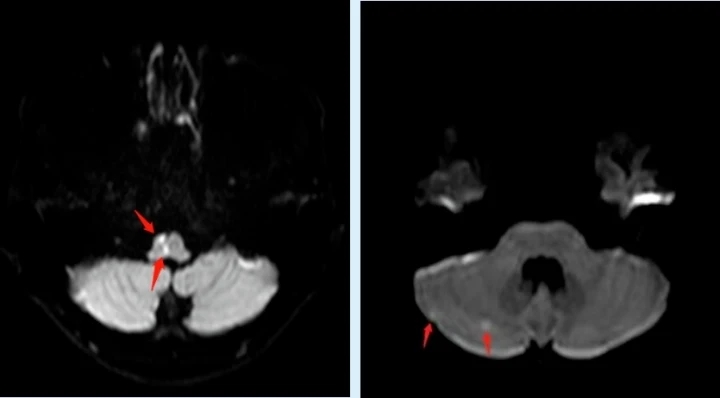

不久前,高三在讀學(xué)生小黃在課間休息時(shí)突然感覺自己左側(cè)肢體麻木、乏力,走路搖搖晃晃的,班主任見狀立即呼叫120送至惠州市第一人民醫(yī)院神經(jīng)內(nèi)科就診,出乎所有人的意料,平時(shí)生活作息規(guī)律、飲食均衡、熱愛運(yùn)動(dòng)且年僅17歲的小黃竟然得了“中風(fēng)”!頭顱MR顯示延髓、右側(cè)枕葉及右側(cè)小腦半球多發(fā)腔隙性腦梗死。

市第一人民醫(yī)院神經(jīng)內(nèi)科一區(qū)主任邱金華介紹,經(jīng)檢查發(fā)現(xiàn),導(dǎo)致這個(gè)小伙子中風(fēng)的原因竟是因?yàn)樗男呐K有個(gè)大小約4mm的“心眼兒”——卵圓孔未閉。

導(dǎo)致小黃中風(fēng)的原因是因?yàn)樾呐K有個(gè)約4mm的“心眼兒”——卵圓孔未閉。